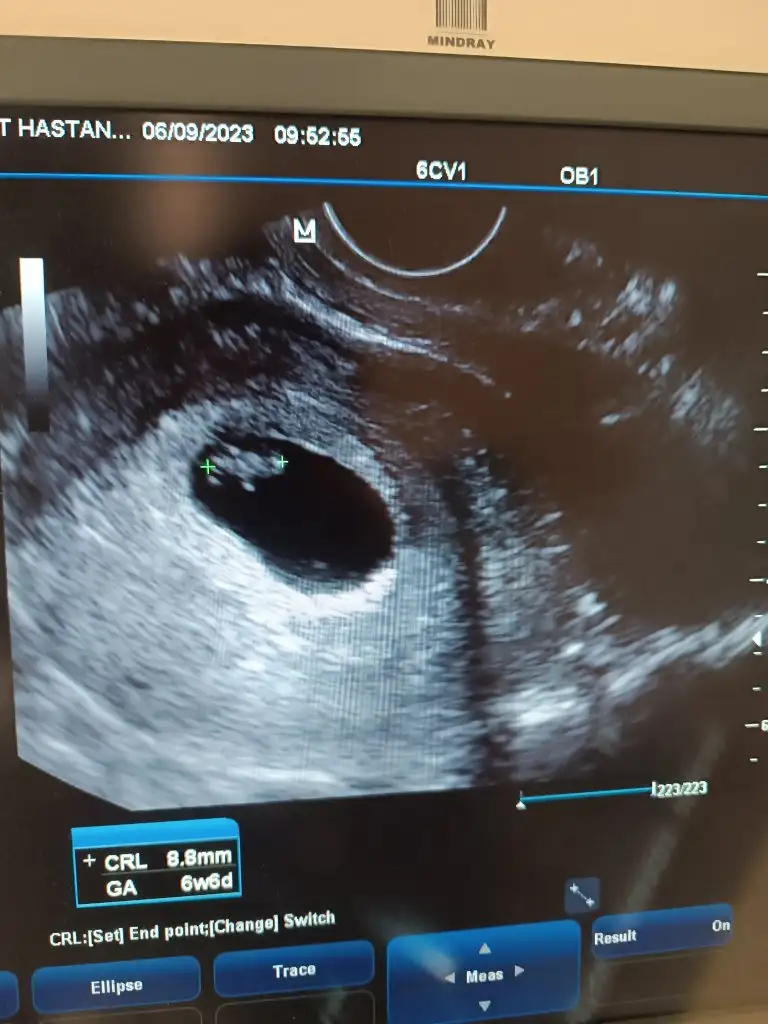

Merhaba bence kız, sağlıkla gelsin inşallahBizi de yorumlarmısınız 6+6 günlük vajinal usg

Merhaba cinsiyeti öğrendiniz mi benim ultrasonda aynı merak ettimBizi de yorumlarmısınız 6+6 günlük vajinal usg